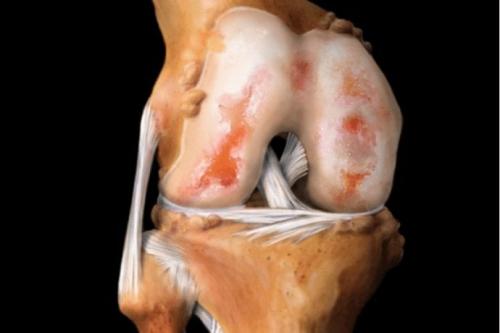

Вид на поражённую хрящевую поверхность.

При артрозе истончается хрящевая соединительная ткань сустава, тем самым травмируя кости

Хрящ колена у некоторых людей начинает разрушаться еще до наступления 30 лет, и происходит это по разным объективным причинам. К 45 годам уже наступает полноценно развивающийся процесс разрушения хрящевой ткани, выражающийся в ее изначальном повреждении и возникновении микротрещин, затем в появлении обширного воспалительного процесса, за которым следует разрастание и деформация костной ткани. Заболевание, у которого есть общий собирательный термин артрит, развивается по нескольким причинам.

Иногда это проникновение инфекционного агента в синовиальную сумку, нередко развитие аутоиммунного процесса без его присутствия. Но всегда это довольно сложная клиническая картина, в которой присутствует как фактор интенсивное кровообращение этой области, разрушение менисков. При недуге отмечаются окружающие хрящ многочисленные полости, в которых свойственно образовываться гнойным затекам.